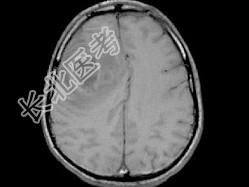

- 单项选择题男,49岁, 头痛、左侧肢体不能活动1周,PE: 左上下肢肌力O级,根据所提供图像, 最可能的诊断是 ( )

A、(右额顶)脑结核

B、(右额顶)脑转移瘤

C、(右额顶)脑脓肿

D、(右额顶)脑膜瘤

E、(右额顶)胶质瘤